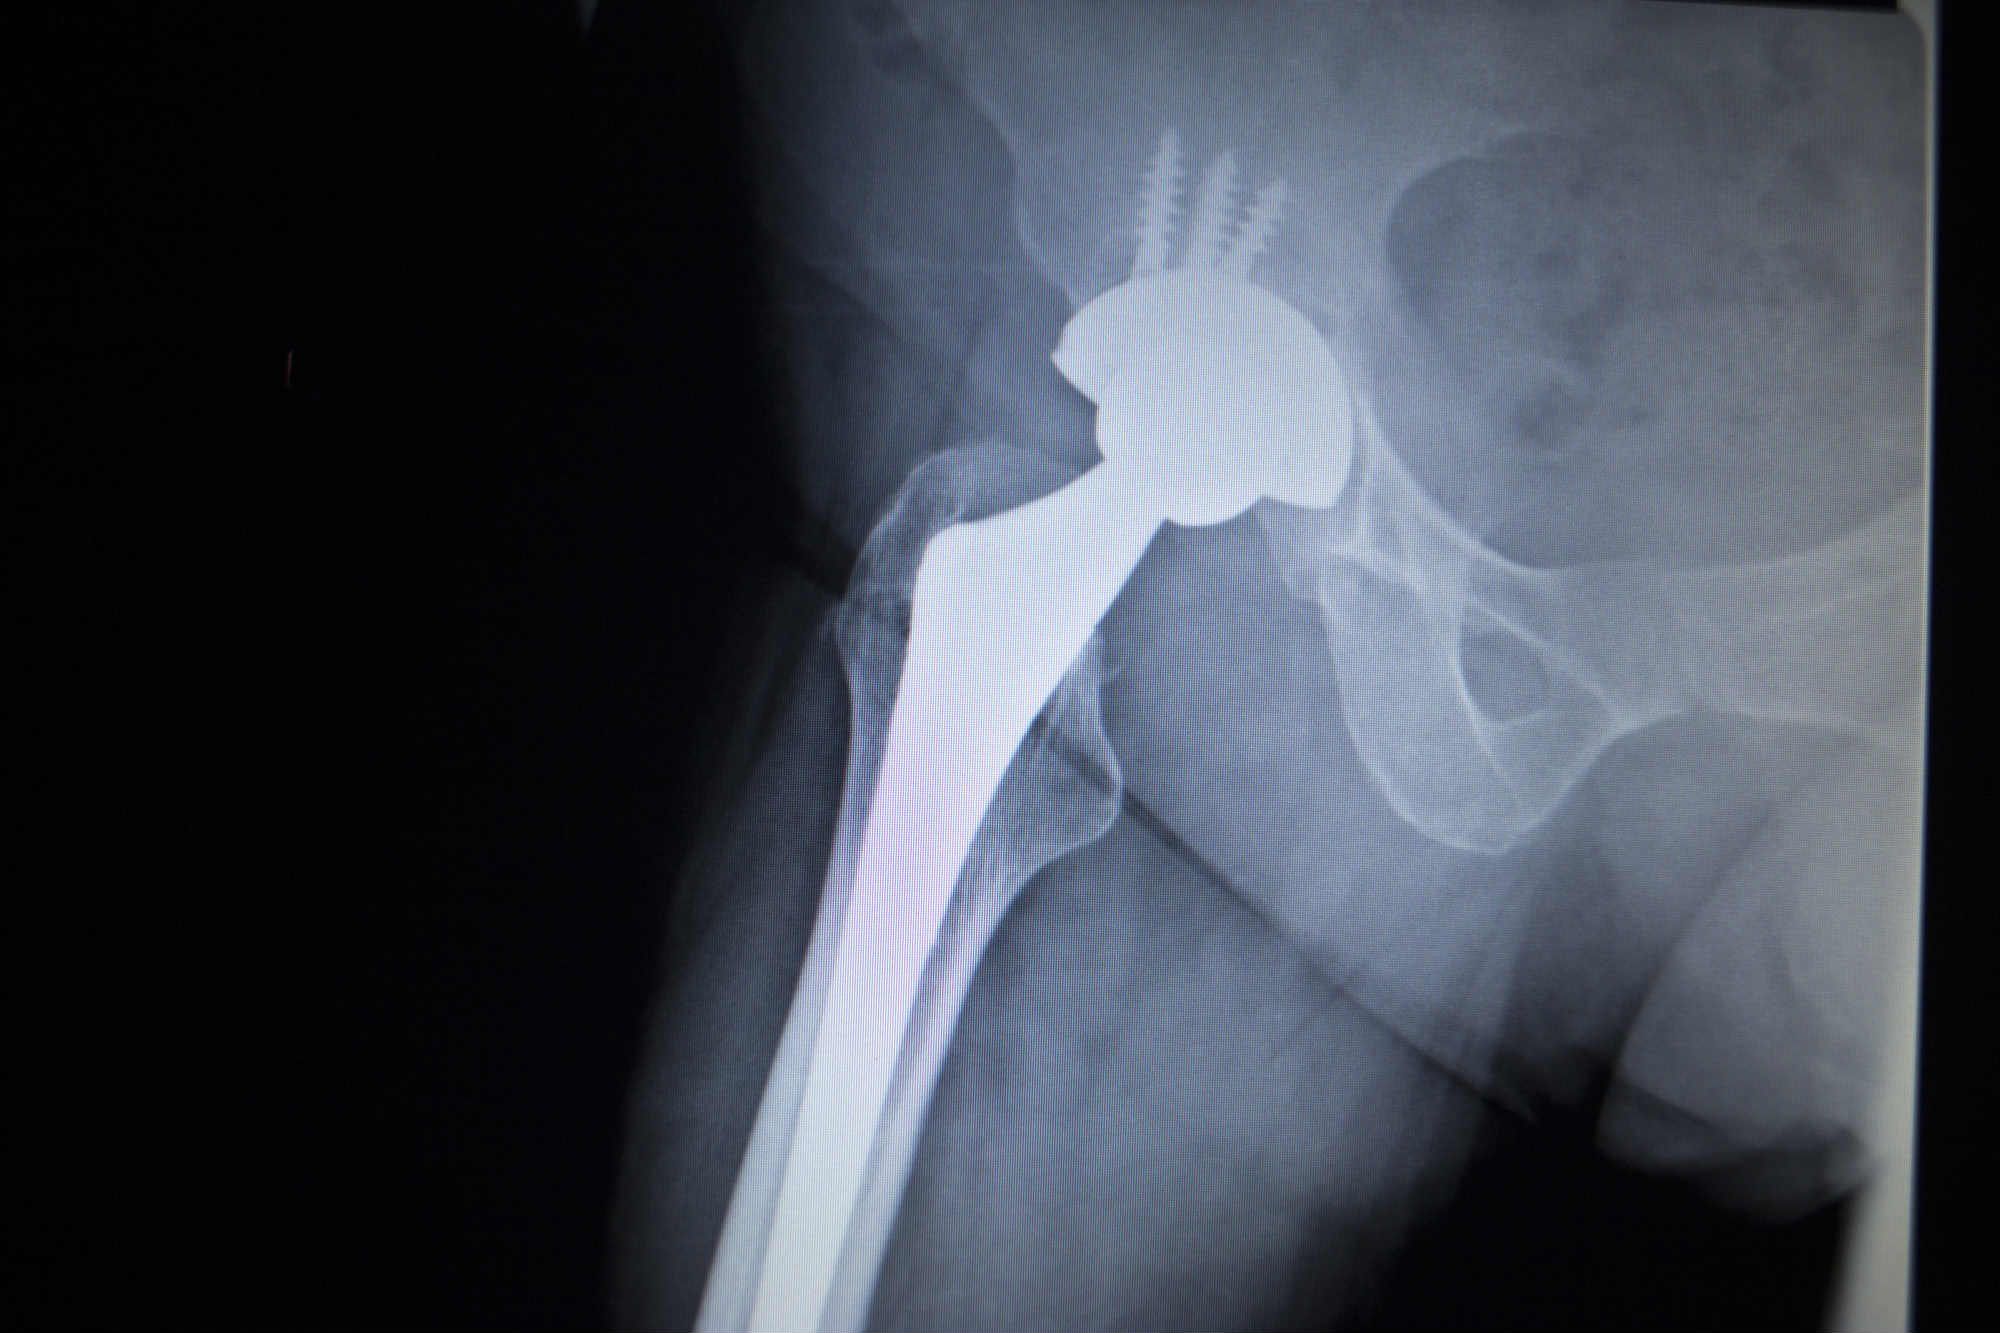

Stryker Hip Replacement Recall List . Please inform users of this urgent. Learn about the latest developments in stryker hip replacement lawsuits involving lfit v40, rejuvenate, abg ii and tritanium devices. Find out the causes, complications, settlements and lawsuits related to the recalls. Please contact your local sales office or your stryker sales representative directly for product replacement and inventory. On 10/15/2021, stryker issued urgent medical device recall notices to customers. Learn about the stryker hip implant recalls involving rejuvenate, abg ii, lfit v40 and accolade tmzf devices. The aaos device recall dashboard provides orthopaedic surgeons with timely recall information that will protect the health and well. Find out if you qualify to file a claim and what injuries are named in the lawsuits. The fda recommends not using or implanting the synovo total hip system, including resurfacing implants, after 2019 due to. Learn about the hip replacement lawsuits filed against stryker and other device makers for complications such as metal poisoning, infection, and nerve damage.

The fda recommends not using or implanting the synovo total hip system, including resurfacing implants, after 2019 due to. Learn about the stryker hip implant recalls involving rejuvenate, abg ii, lfit v40 and accolade tmzf devices. On 10/15/2021, stryker issued urgent medical device recall notices to customers. Find out if you qualify to file a claim and what injuries are named in the lawsuits. Learn about the latest developments in stryker hip replacement lawsuits involving lfit v40, rejuvenate, abg ii and tritanium devices. Please contact your local sales office or your stryker sales representative directly for product replacement and inventory. Please inform users of this urgent. The aaos device recall dashboard provides orthopaedic surgeons with timely recall information that will protect the health and well. Learn about the hip replacement lawsuits filed against stryker and other device makers for complications such as metal poisoning, infection, and nerve damage. Find out the causes, complications, settlements and lawsuits related to the recalls.

Stryker Hip Replacement Recall List Learn about the stryker hip implant recalls involving rejuvenate, abg ii, lfit v40 and accolade tmzf devices. Learn about the hip replacement lawsuits filed against stryker and other device makers for complications such as metal poisoning, infection, and nerve damage. Please inform users of this urgent. Find out the causes, complications, settlements and lawsuits related to the recalls. On 10/15/2021, stryker issued urgent medical device recall notices to customers. The aaos device recall dashboard provides orthopaedic surgeons with timely recall information that will protect the health and well. Learn about the stryker hip implant recalls involving rejuvenate, abg ii, lfit v40 and accolade tmzf devices. Find out if you qualify to file a claim and what injuries are named in the lawsuits. Please contact your local sales office or your stryker sales representative directly for product replacement and inventory. The fda recommends not using or implanting the synovo total hip system, including resurfacing implants, after 2019 due to. Learn about the latest developments in stryker hip replacement lawsuits involving lfit v40, rejuvenate, abg ii and tritanium devices.